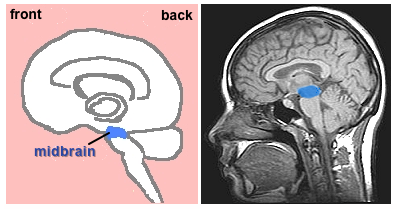

C. Midbrain

midbrain

Segment of top of the brainstem lying between the pons and the forebrain.

• Sensitive to orientation of individual in space; works with voluntary muscle movement, e.g., moving head to respond to someone's call or a strange sound in the environment; tracking an object like a baseball to catch it

• Dopamine-releasing neurons project from the midbrain into the forebrain. The gradual death of these neurons is associated with the development of Parkinson's Disease.